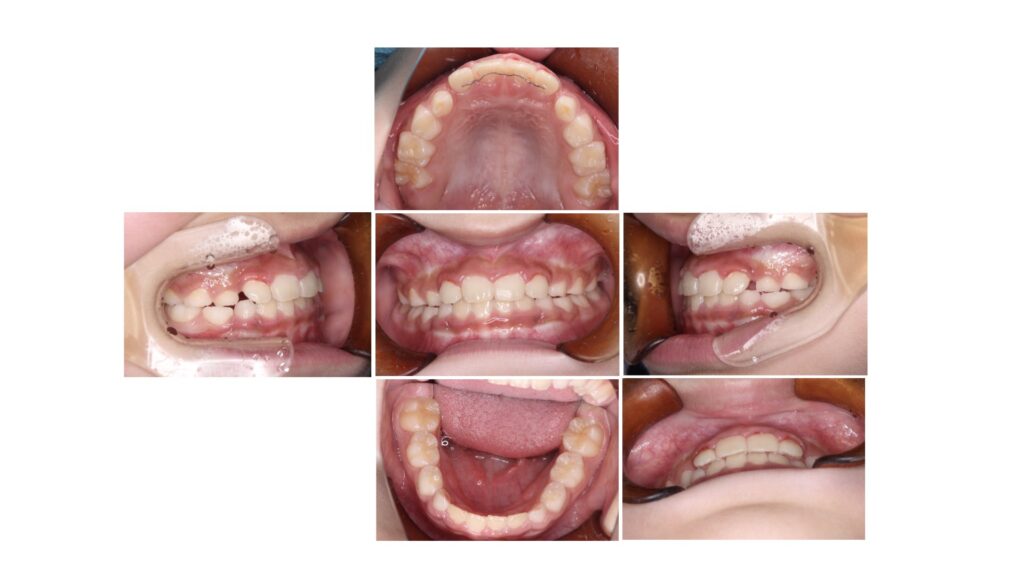

以下にさきほどのレントゲン写真のお子様の乳歯と永久歯の大きさの違いを本人の歯の写真で見ていただきます。

青矢印が乳歯、赤矢印は永久歯です。写真も倍率の違いや撮影アングルによって見え方は異なりますが参考にはなります。

「レントゲンでは乳歯の方が永久歯よりも大きく見えていた」のが実際は「乳歯の方が永久歯よりも大きい」のです。

実は永久歯の方が乳歯よりも大きくなるのは前から数えて1〜3番目の永久歯までです。4番目、5番目に関しては永久歯の方が乳歯よりも小さくなるのです。

黄色の円で囲った部分の歯茎が膨らんでみえますでしょうか?

乳歯よりも永久歯の方が歯根(歯の根っこ)は大きくなるため、骨の幅は「永久歯が生えてくるタイミング」で大きくなっていきます。例にあげた歯は犬歯と呼ばれますが9歳以降に生えてくる目安の永久歯です。「6歳までに顎の成長が終わるので勝負は6歳まで!」という話には根拠がないことを示しています。